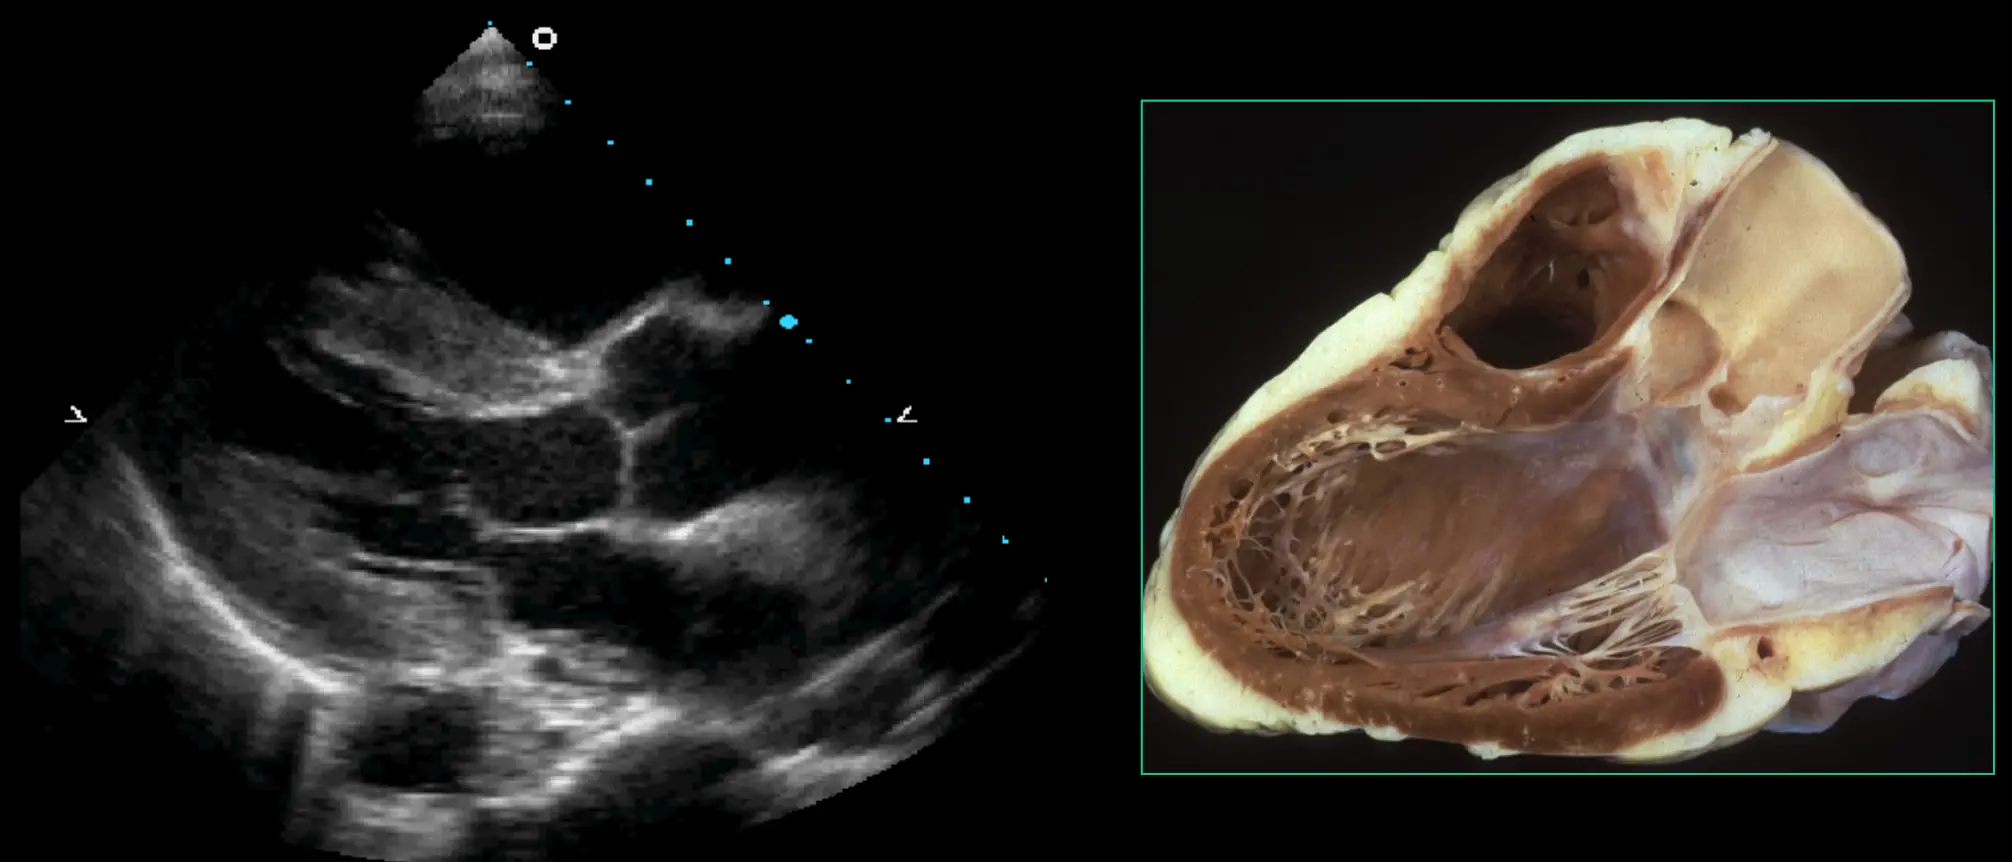

Basic Echo Views

PLAX